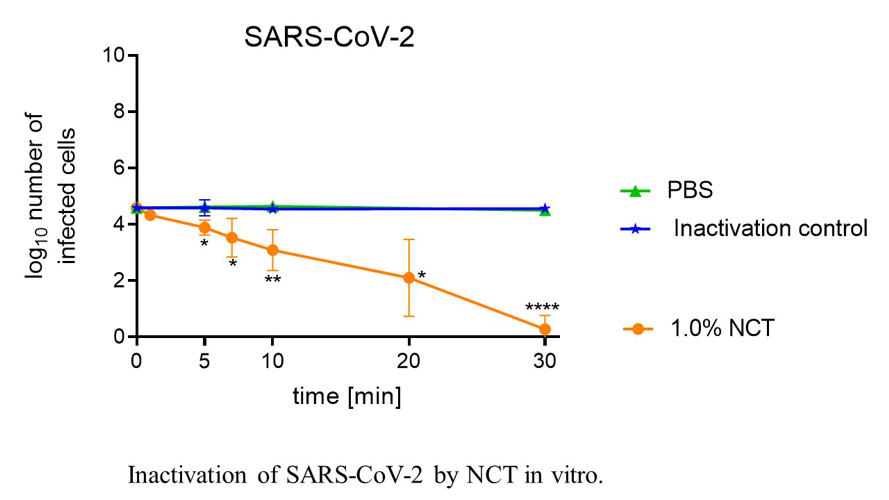

N-chlorotaurine

N-chlorotaurine (NCT), a long-lived oxidant produced by activated human leukocytes, has been synthesised as sodium salt in our laboratory and is being investigated as a new antiseptic for the topical treatment of infections of multiple body regions, including sensitive ones.

Basic research currently comprises its microbicidal activity against viruses including SARS-CoV-2, multiresistant bacteria and fungi biofilms. Latest clinical investigations cover the bronchopulmonary system (confirmatory phase II inhalation of NCT in Covid-19 patients planned) as well as various other topical applications, such as to the skin and mucous membranes, the eye, the ear-nose-throat region, the urinary tract and organ abscesses. Advantages of NCT include high tolerability, a broad spectrum of activity against all strains of pathogens without inducing resistance, inactivation of virulence factors of pathogens, enhancement of microbicidal activity in the presence of body fluids and anti-inflammatory effects.

- Leiter H, Toepfer S, Messner P, Rabensteiner M, Gostner JM, Lackner M, Hermann M and Nagl M: Microbicidal activity of N-chlorotaurine can be enhanced in the presence of lung epithelial cells. Journal of Cystic Fibrosis. doi: 10.1016/j.jcf.2020.03.005. March 2020;